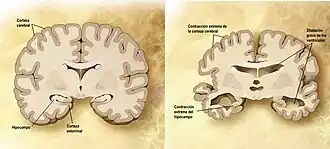

Comparación entre un cerebro normal (izquierda) y un cerebro afectado de alzhéimer (derecha). | ||

La enfermedad de Alzheimer se caracteriza por la pérdida de neuronas y sinapsis en la corteza cerebral y en ciertas regiones subcorticales. Esta pérdida resulta en una atrofia de las regiones afectadas, incluyendo una degeneración en el lóbulo temporal y parietal y partes de la corteza frontal y la circunvolución cingulada.[46]